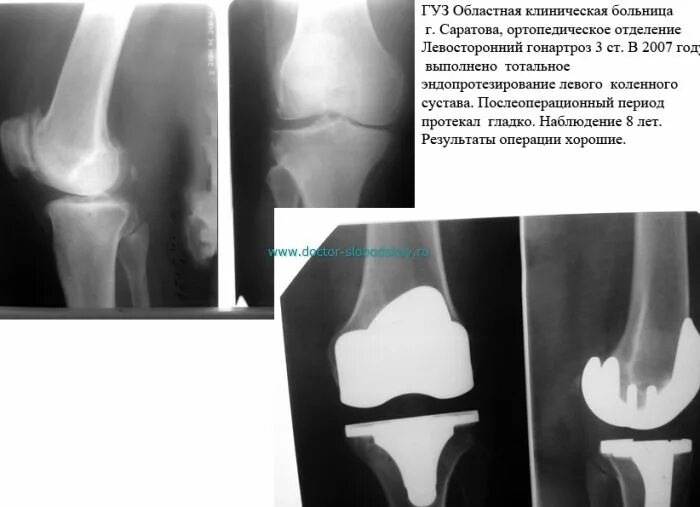

Дают инвалидность после замены сустава